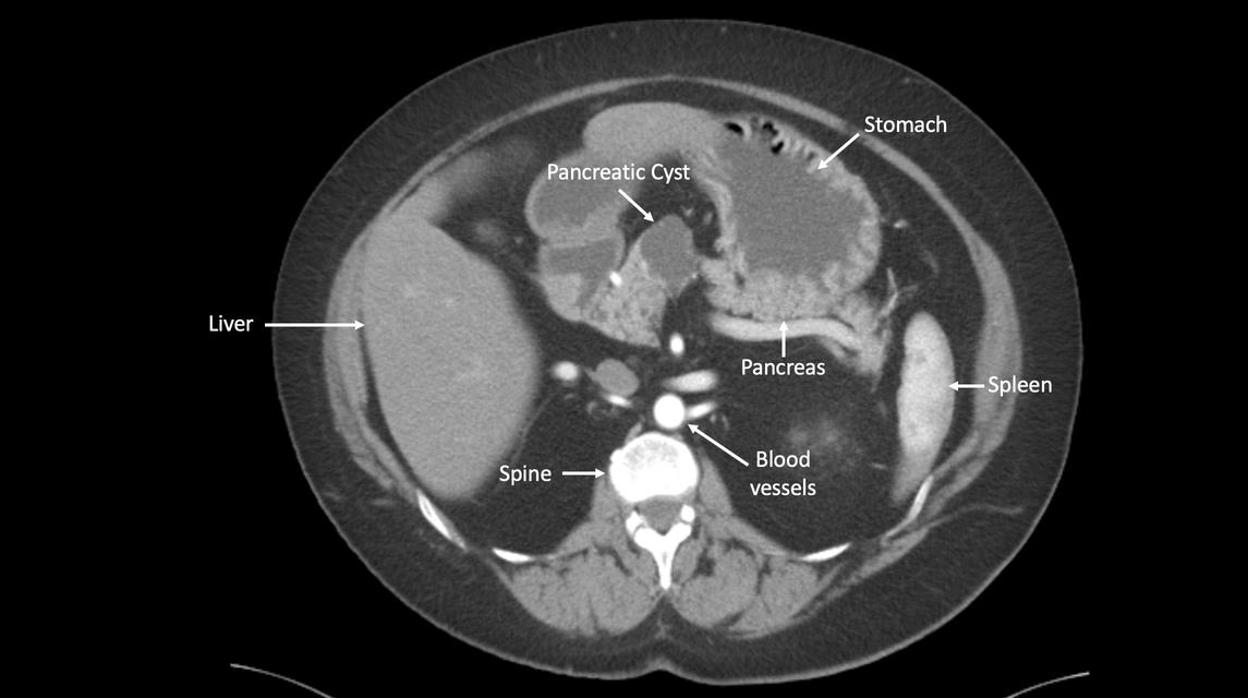

Imagen de un tumor en el páncreas